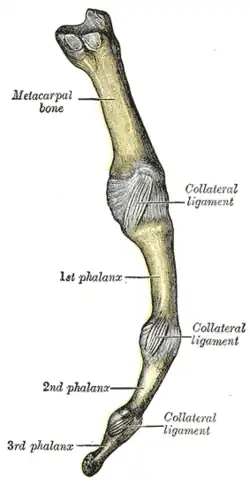

Metacarpophalangeal articulation and articulations of digit. Volar aspect. Metacarpophalangeal articulation and articulations of digit. Ulnar aspect.

Metacarpophalangeal articulation and articulations of digit. Ulnar aspect.